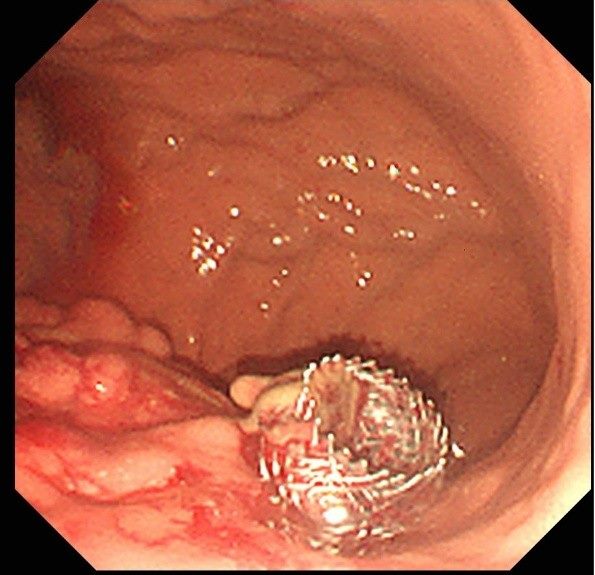

北市聯醫和平婦幼院區醫療團隊悉心照護該名病患後,成功將其從加護病房轉出,感染也逐步控制。然而,胰臟炎併發症形成的假性囊腫與膿瘍卻成為後續治療的棘手挑戰。在經過六周的抗生素治療後,始由消化內科主治醫師黃柏翰攜手內視鏡室團隊,為這位病患成功執行內視鏡超音波導引下胰臟膿瘍金屬支架引流術。

醫師黃柏翰說,這項微創手術透過內視鏡,將金屬支架精準地放置於胰臟病灶處並與胃內建立引流通道,有效排出壞死組織或囊液,成功避免了傳統外科手術的巨大創傷與高風險,為病患帶來治療新希望。

黃柏翰強調,這項新技術的成功,代表和平婦幼院區在處理複雜胰臟疾病的能力已邁入新里程碑。藉由內視鏡超音波精準定位後金屬支架的置放,能以更安全、更有效的方式,幫助那些因胰臟炎併發症而飽受折磨的病患。